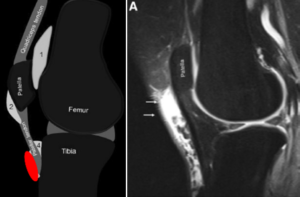

膝滑液包炎とは、膝の腫れや炎症のことです。 滑液包、皮膚と腱、または腱と骨の間に位置する液体で満たされた小さな嚢。

「Bursae」とはラテン語でバッグを意味します。これらのバッグは小さな枕のように機能し、体のさまざまな関節の衝撃を和らげます。滑液包炎はこれらの嚢が炎症を起こすと発症します。 2018年調査と説明します。関節の周囲に体液が溜まる場合があり、これを滲出液といいます。

膝の場合、滑液包は、膝を硬い面に置いたときに膝を保護するのに役立ちます。これは、軟組織と骨の間の摩擦を軽減するのに役立ちます。